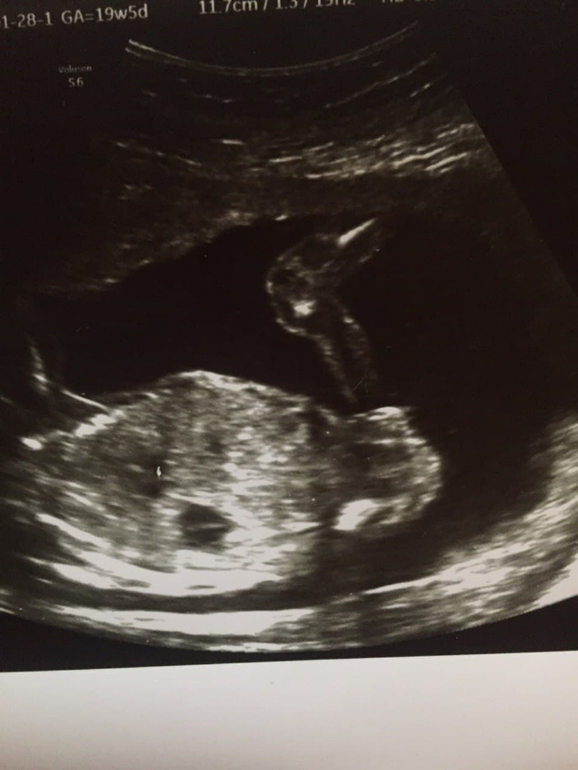

Девочка или Мальчик?

Распечатали снимки пузожителя 17 недель, предположили девочку ) Может ли быть мальчик ? У кого было что пистончик например лежал на пузике и не было видно, а яички принимали за половые губы ) или уже 100 % доча )

На 2 фото если это ножки и вид снизу, то точно девочка. Там три полоски одна под другой, так у девочек на узи половые органы выглядят)

На девочку похоже. Была такая картинка, что у мальчика под углом 45 градусов бугорок будет, а у девочки прямо